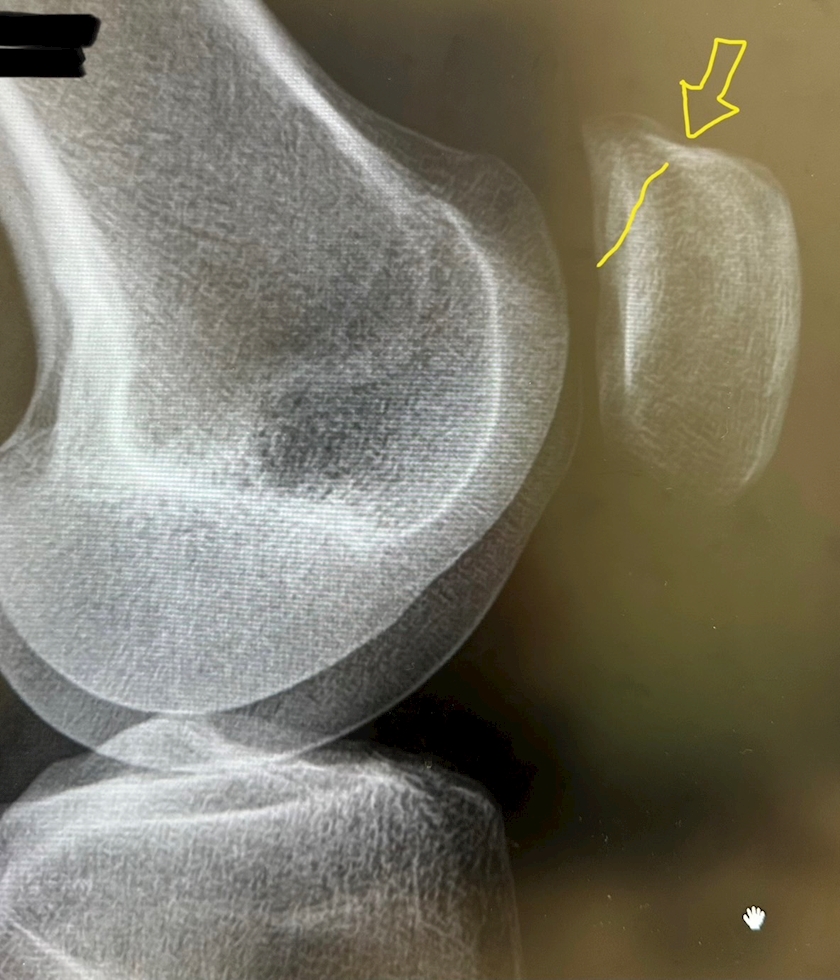

自分の膝の骨を

初めて見たので

撮らせてもらった😳✨

いやん、すけすけ💖

矢印のところに

うすーくヒビが

入ってるらしい。

3週間くらいかかるねー

でも綺麗な骨だよ!

お褒めいただきました🥰

くっつくのを待ちます。